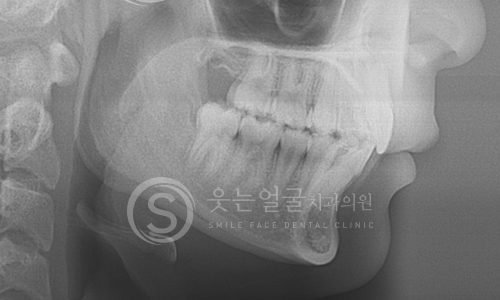

뼈 이식이나 발치 즉시 식립 등 까다로운 조건에서도 정밀 진단과

체계적인 시술 시스템으로 환자 맞춤형 치료를 제공합니다.

• 고난도 임플란트 전문 진료

웃는얼굴치과는 난이도가 높은

임플란트 수술까지 정밀한 진단과 계획을

바탕으로 안전하게 치료합니다.